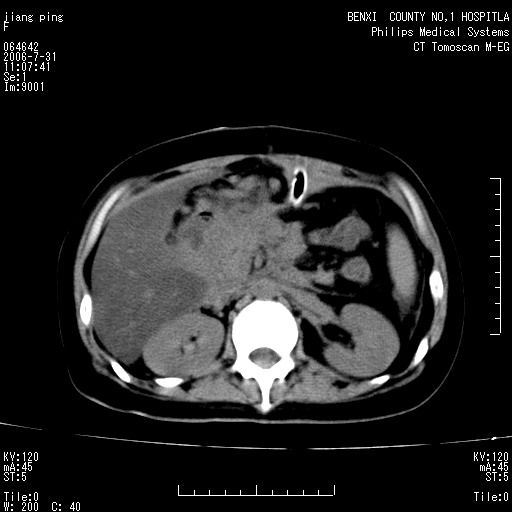

以下是引用晓杰在2006-8-1 9:01:00的发言:[br]支持营养不良导致脂肪肝。[br]胰头增大界限不清,考虑为胰腺炎破坏十二指肠粘膜、肠壁增厚、肠腔狭窄,并与胰头粘连所致

以下是引用jiajie在2006-7-31 20:34:00的发言:[br]支持营养不良导致脂肪肝。[br]胰头增大界限不清,考虑为胰腺炎破坏十二指肠粘膜、肠壁增厚、肠腔狭窄,并与胰头粘连所致。